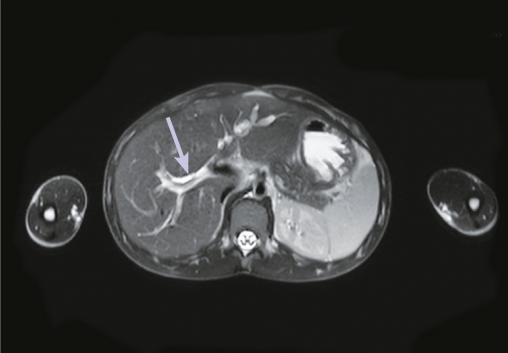

Ce garçon de 16 ans consultait pour des douleurs abdominales et des vomissements. En outre, il décrivait l’élimination de grands vers avec les selles. À l’examen clinique, il était légèrement dénutri. L’hémogramme montrait une hyperéosinophilie à 616/mm3. La tomodensitométrie abdominale montrait une image hyperdense au sein d’une dilatation des voies biliaires intrahépatiques (fig. 1 ). L’imagerie par résonance magnétique hépatique montrait un ascaris en hyposignal linéaire dans les voies biliaires intrahépatiques (fig. 2 ). Le patient était traité avec succès par albendazole.